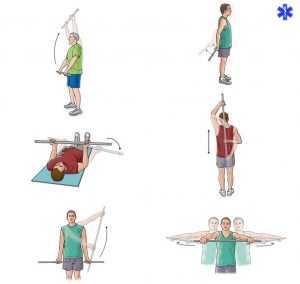

Смотрите в видео упражнения для реабилитации при переломе ключицы:

Как лечить и проводить восстановление поврежденной кости должен решать травматолог. Не следует самостоятельно делать упражнения, применять народные средства, употреблять медицинские препараты.

Для скорейшего выздоровления доктором назначается реабилитация после перелома ключицы. В нее входит — массаж, физиотерапевтические процедуры, ЛФК при переломе ключицы, диета и прием витаминных комплексов.

Упражнения или комплекс специальных лечебных упражнений следует проводить под наблюдением реабилитолога.

Лечение данного перелома в домашних условиях разрешается, только если повреждение не имеет осложнений. В период реабилитации, после согласования с лечащим врачом, часть мероприятий можно проводить дома. Это может быть гимнастика, лечебная физкультура, массаж.

Восстановительный период

Реабилитация является частью лечебного процесса. Рука после длительного периода неподвижного состояния должна разрабатываться. Восстановление после перелома ключицы должно быть комплексным. Применяться должны водолечение, массаж, физиопроцедуры. Специально разработанные комплексы покажет врач, их можно делать уже с гипсом. Это будут пассивные упражнения, но они будут способствовать усилению кровотока в месте травмы.

Обязательно надо выполнять общеукрепляющие комплексы для всего организма, заниматься ходьбой, дышать по возможности свежим воздухом. Самое плохое, что может сделать пациент для себя, – долго лежать в постели (если доктором не прописан постельный режим).

Очень важным этапом является реабилитация после перелома ключицы, состоящая из нескольких моментов. В периоде реабилитации последствия будут минимальны, если использовать физиопроцедуры, гимнастику и массаж.

Гимнастика и массаж

Массаж расширяет сосуды, улучшая кровоток в месте перелома, костная мозоль превращается постепенно в кость. На курс необходимо от 10 до 15 процедур, выполняемых каждый день опытным специалистом. Процедура выполняется не раньше чем через 2 часа после еды, в противном случае пища способна попасть в дыхательные пути. Длительность процедуры составляет от 15 до 30 минут.

Гимнастика является важным этапом восстановления после любого перелома. Выполняться она должна постепенно, начиная с простых движений без нагрузки и под контролем опытного специалиста. По мере заживления кости и тренированности мышц нагрузка увеличивается.

Реабилитация

Если человек больше месяца сломал ключицу, то процессы восстановления костной ткани к этому времени завершаются. Наступает этап разработки. Период восстановления после перелома ключицы без смещения занимает 3-6 месяцев. Физические нагрузки разрешены уже через 6 недель, но начинать нужно с малого. Наиболее простыми методами восстановить функции руки считаются лечебная физкультура и физиотерапия.

Тяжелее дается реабилитация после осложненного перелома ключицы со смещением. Врач подбирает схему терапии, исходя из возраста пациента и последствий травм. Так, стандартная реабилитация после перелома ключицы включает лечебный массаж, прием сероводородных ванн и плавание. Чрезмерные нагрузки при восстановлении ключицы после перелома со смещением исключены.

Восстановительный процесс после операции затягивается. Чтобы рука восстановилась полностью, необходимо от 6 до 12 месяцев. Некоторое время после извлечения металлоконструкций следует проводить обработку кожи. Сроки восстановления определяются и возрастом пациента – после 40 лет реабилитация требует больше времени.

Физиотерапия

ЛФК при переломе ключицы играет основную роль в период реабилитации. Показаны активно-пассивные покачивания, вращения предплечья, движения пальцами и кистью. Расширить комплекс упражнений для ключицы при переломе призваны дыхательная гимнастика, тренировка мелкой моторики, общетонизирующий бег. К нагрузкам подходят осторожно. Ослабленная костная ткань подвержена травматизму. Занятия на тренажерах или с весом допустимы через 1,5 месяца после снятия гипса.

ЛФК при переломе ключицы играет основную роль в период реабилитации. Показаны активно-пассивные покачивания, вращения предплечья, движения пальцами и кистью. Расширить комплекс упражнений для ключицы при переломе призваны дыхательная гимнастика, тренировка мелкой моторики, общетонизирующий бег. К нагрузкам подходят осторожно. Ослабленная костная ткань подвержена травматизму. Занятия на тренажерах или с весом допустимы через 1,5 месяца после снятия гипса.

Повысить эффективность ЛФК после перелома сумеют магнитотерапия и лекарственный электрофорез. Еще до проведения лечебной физкультуры рекомендуется делать СУФ-облучение для расслабления мускулатуры и снятия отека.

Эффективность доказала УВЧ-терапия. Она прогревает ткани, улучшает кровоснабжение и стимулирует регенерацию. Длительность процедуры – 10-15 минут, сеансы повторяют 10 дней. С помощью ультразвукового воздействия удастся улучшить трофику тканей, нормализовать клеточный метаболизм, предупредить рубцевание в случае открытых ран.